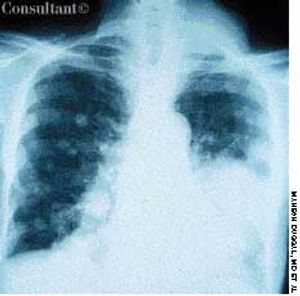

A 2-month history of cough sent a 62-year-old woman for medical evaluation. The patient denied fever, chills, and rigors but reported seeing streaks of blood in her sputum during the past month. The patient had undergone a right nephrectomy 4 years earlier for renal cell carcinoma.